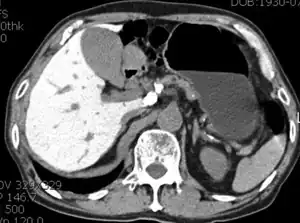

Side effects of amiodarone include various pulmonary effects.[22] The most serious reaction that is due to amiodarone is interstitial lung disease. Risk factors include high cumulative dose, more than 400 milligrams per day, duration over two months, increased age, and preexisting pulmonary disease. Some individuals were noted to develop pulmonary fibrosis after a week of treatment, while others did not develop it after years of continuous use. Common practice is to avoid the agent if possible in individuals with decreased lung function.

The most specific test of pulmonary toxicity due to amiodarone is a dramatically decreased DLCO noted on pulmonary function testing.